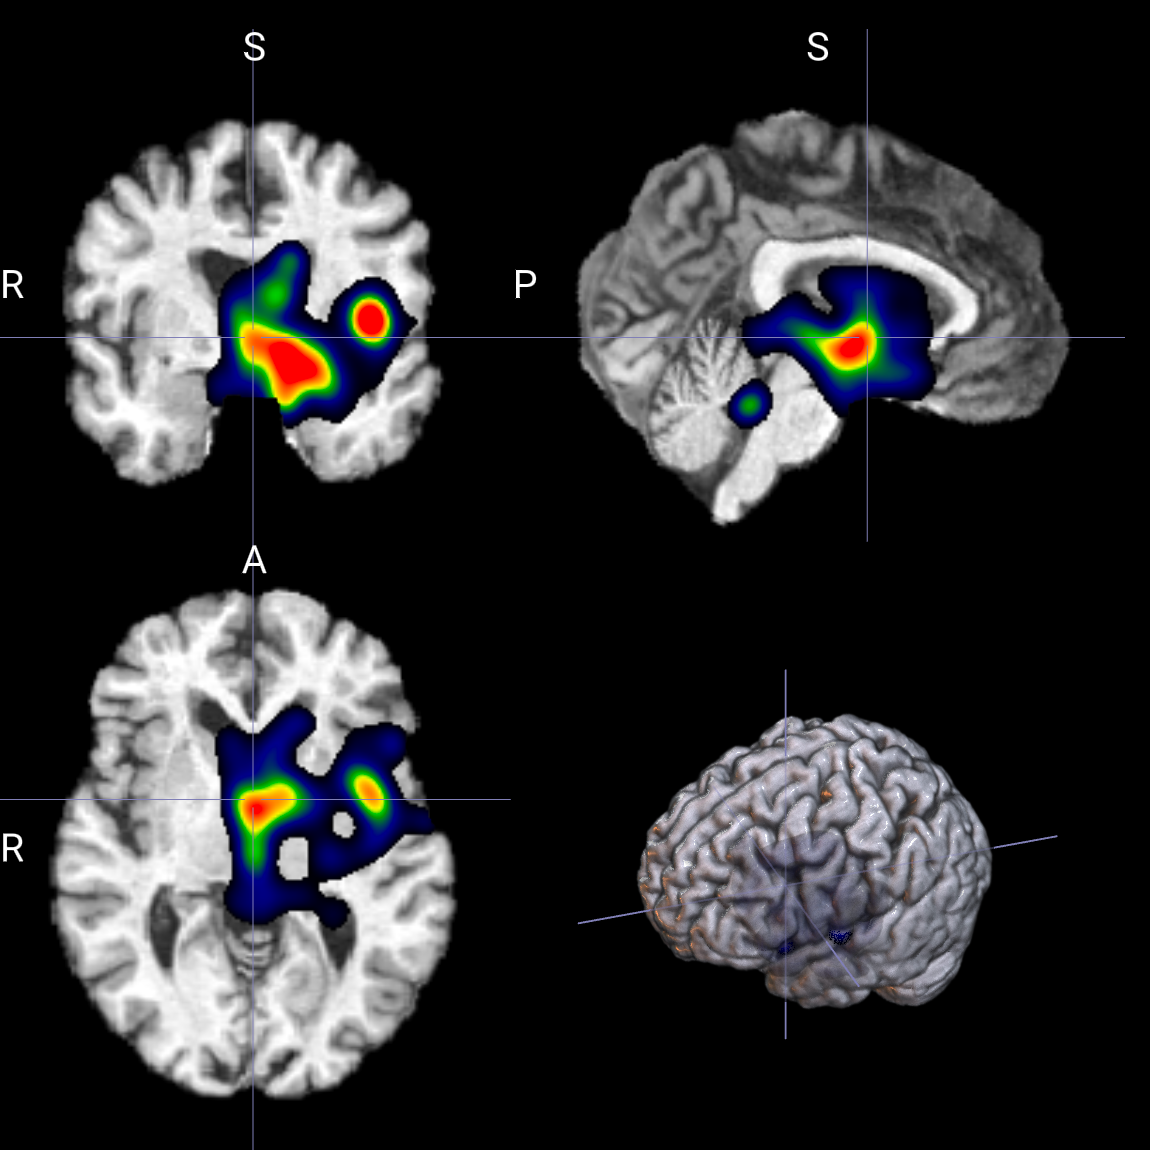

输出示例